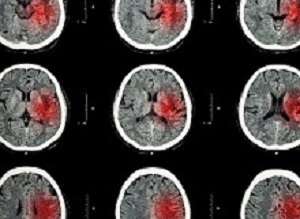

StrokeA simple test, the Montreal Cognitive Assessment, taken within a week of a stroke may help predict how well people will have recovered up to three years later, according to a German study.